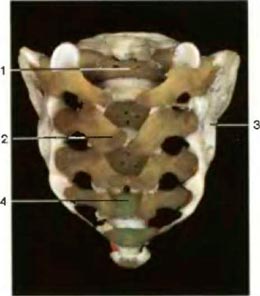

Окостенение крестца. (Вид спереди) Видны пять позвонков,которые всё еще продолжают сростаться друг с другом |

1. Костная ткань (тело позвонка)

2. Хрящевая ткань (Боковые эпифизы)

3. Межпозвонковые диски

1. Textus osseus - corpus

vertebrae

2. Textus cartilagineus

3. Discus intevertebralis

Окостенение крестца (

Вид сзади) Окостенение крестца (

Вид сзади) |

1. Костная ткань (центр окостенения)

2. Дуги позвонков (срослись не полностью)

3. Хрящевая ткань (боковые эпифизы)

4. Крестцовый канал

1. Textus osseus

2. Arcus vertebrae

3. Textus cartilagineus

4. Canalis sacralis